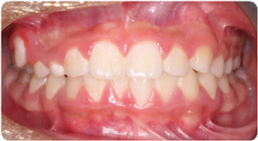

Each case shows the front view and an arch or side view, before and after BioLign Method-guided treatment.

All cases treated within 6–12 months.

Crowding with irregular gaps resolved into even alignment